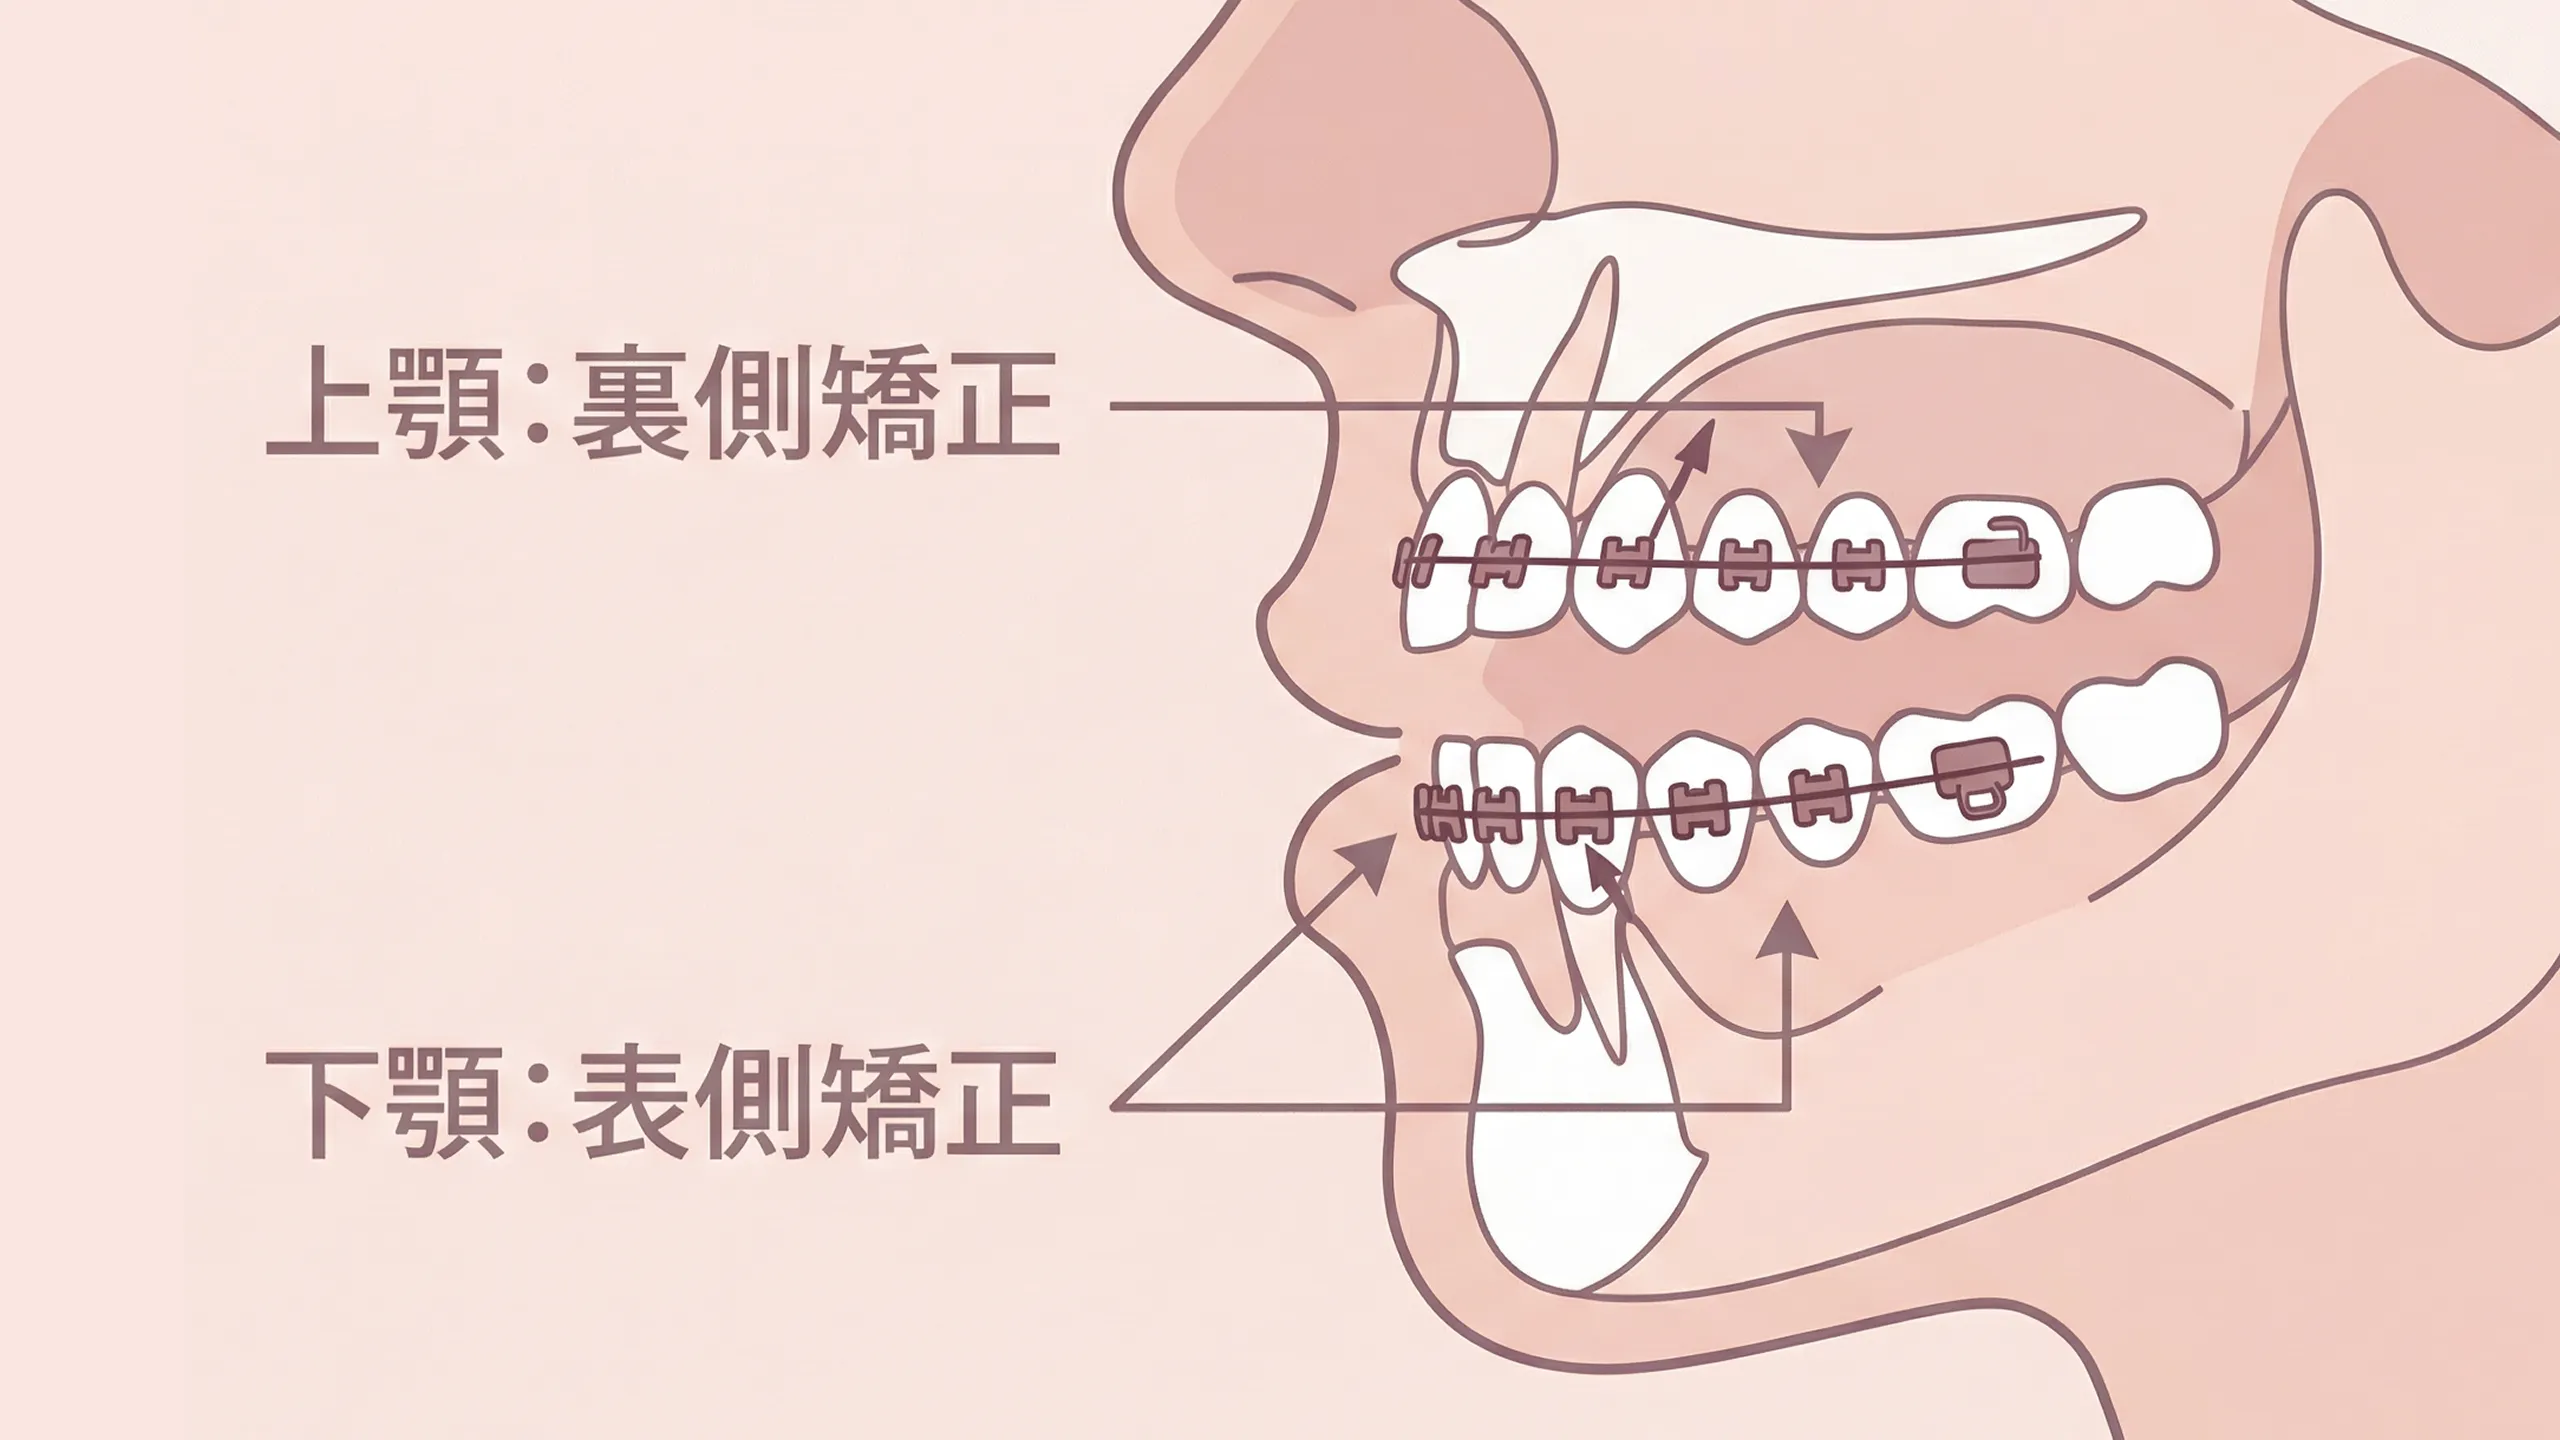

ハーフリンガル矯正

上顎は裏側、下顎は表側とするハイブリッド方式。審美性と発音・清掃性のバランスが特長です。フルリンガルより費用を抑えつつ、見え方の配慮が可能。装置設計が複雑になるため、診断とワイヤーベンディングの技量が重要。適応や期間は認定医の評価に基づきご提案します。